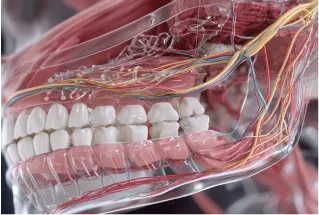

インプラントは人工歯根を顎の骨に埋め込む外科処置です。

以下のような情報が今後の治療の鍵になります。

現在の骨の状態

神経・血管の位置

噛み合わせや歯周病の状態

これらを手術前に正確に把握しておくことで、失敗や後戻りのリスクを大きく軽減できます。

歯科用CTによる3D精密診断

歯科用CTは、レントゲンでは見えづらい顎の骨や神経の位置を、3Dの立体画像で確認できる機器です。

骨の厚み・幅・密度

インプラントを埋めるのに十分な骨があるかチェックできます

神経や血管の位置

インプラント埋入時に神経を傷つけないよう、ミリ単位で確認できます。

精密なインプラント治療のために、「見える化」するのが歯科用CTの役割です。